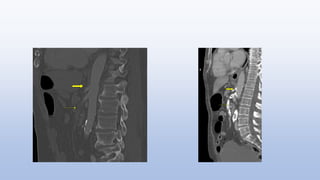

Distended featureless loops of small bowel with wall

thickening (arrow) and separation of the bowel loops

Air within the wall of the ascending colon (arrow)

Radiological Evaluation Distended featurelessloops of small bowel with wall thickening (arrow) and separation of the bowel loops Air within the wall of the ascending colon (arrow)